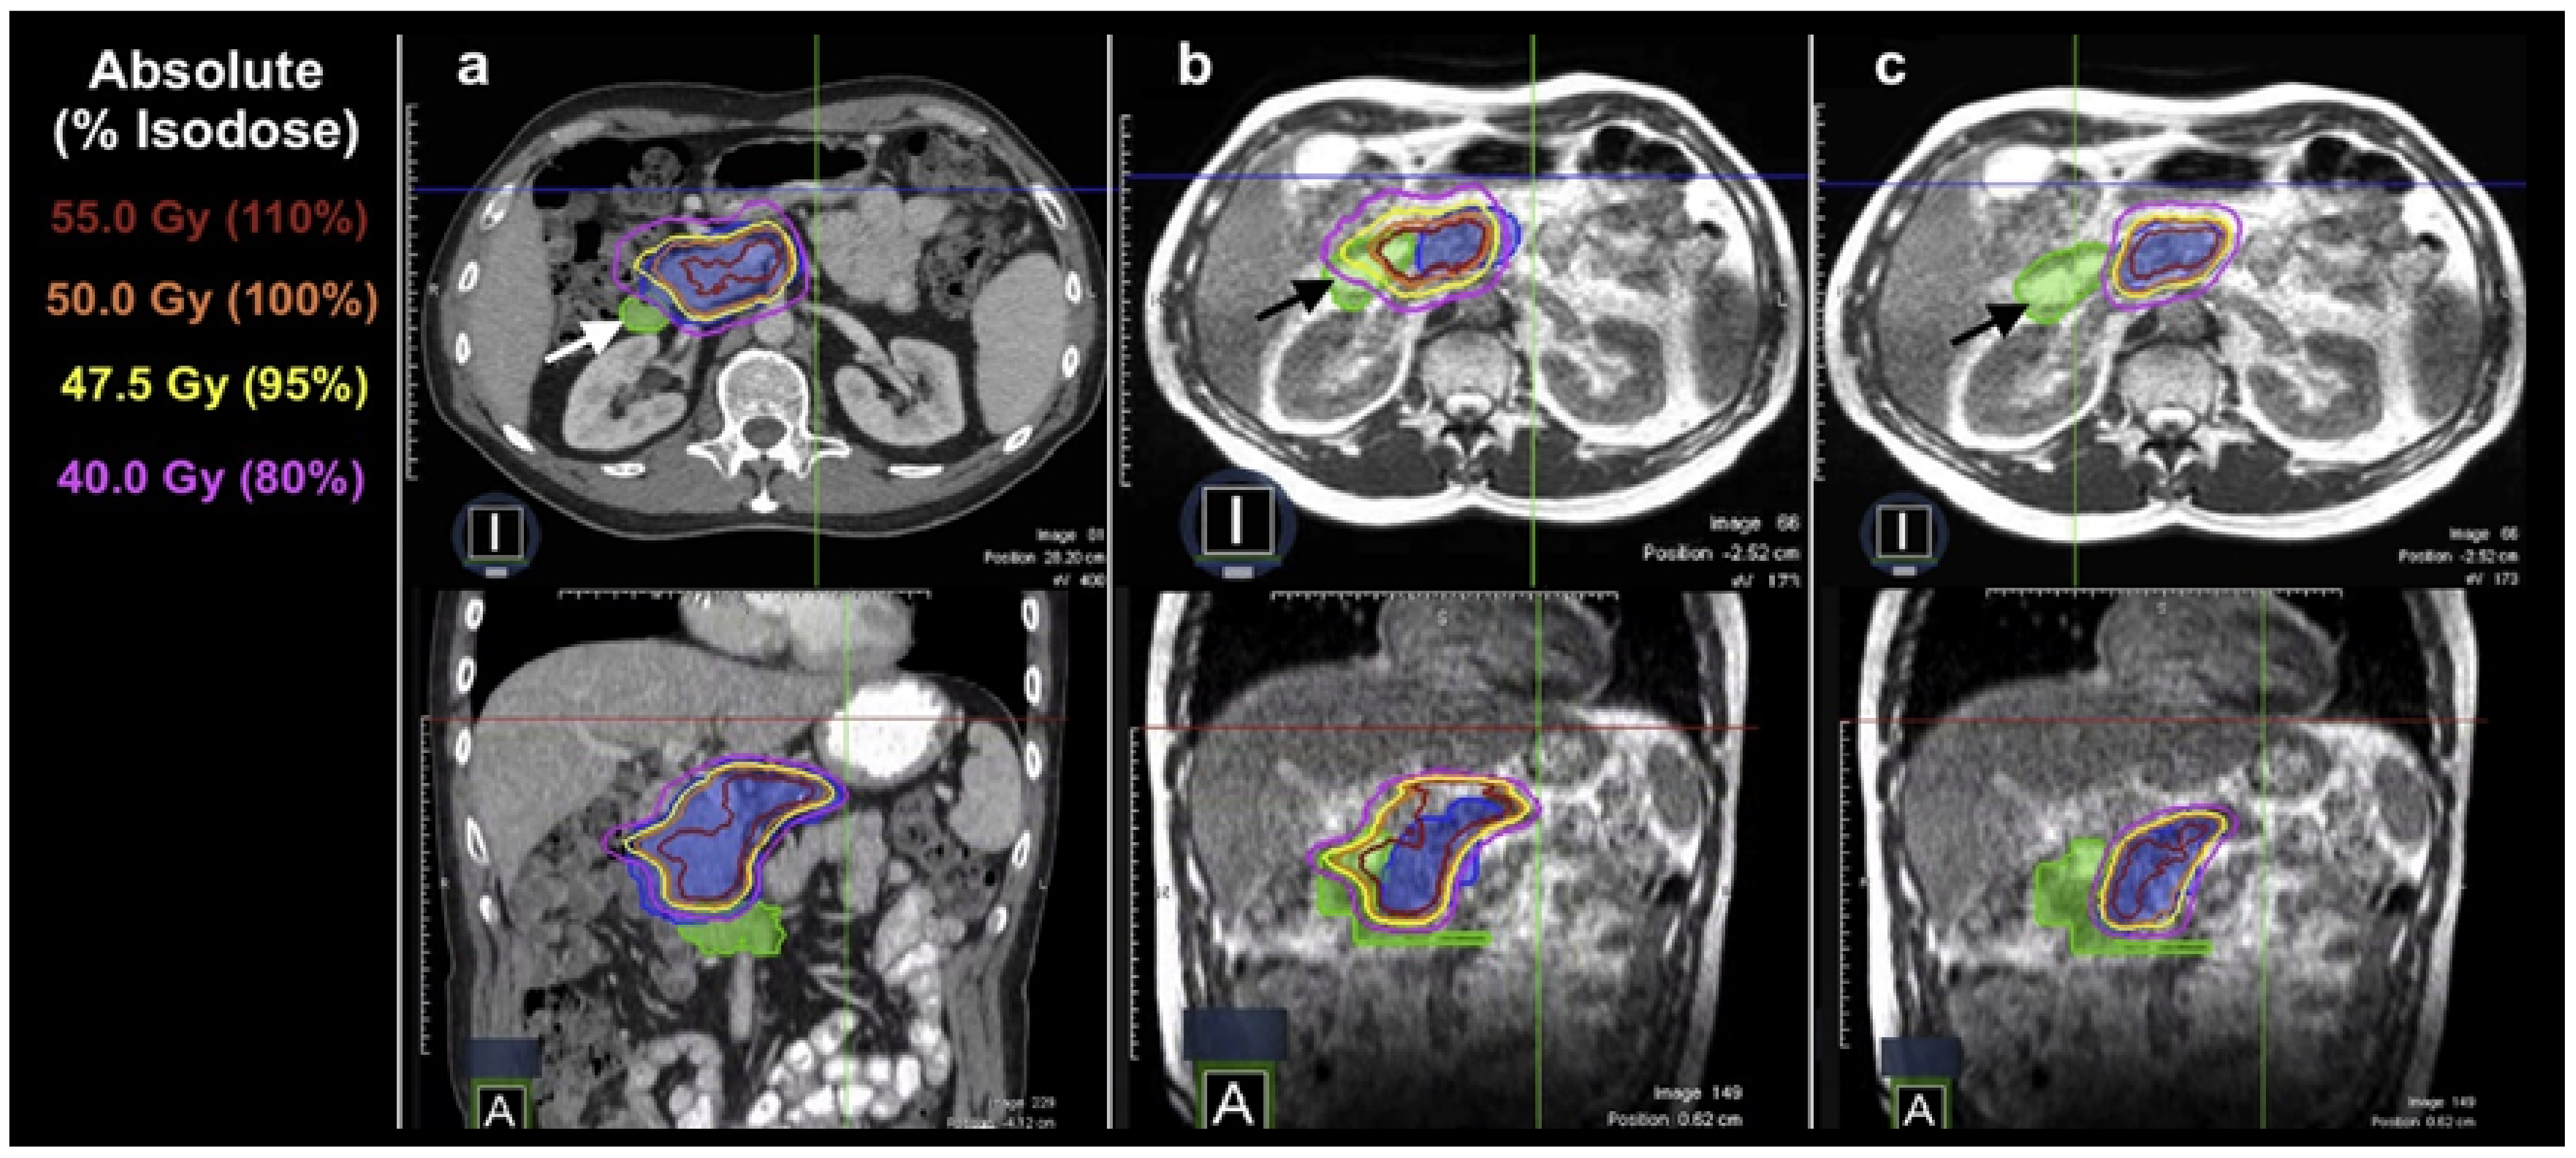

MRI’s exceptional ability to distinguish soft tissues allows for the accurate evaluation of anatomical changes, making it an optimal tool for online adaptive replanning in radiotherapy. As shown in an example case in Figure 4, MR-LINAC provides good soft-tissue contrast, highlighting the daily changes in the relative position and shape of the tumor and OARs for a pancreatic cancer case, and plan adaptation helps maintain the optimal tumor coverage vs. OAR sparing.

Figure 4.

(a) Initial plan met all organ-at-risk constraints for a patient with a pancreatic tumor (blue color wash) based on the anatomy from the initial CT simulation. (b) Application of the plan to the daily MRI set resulted in a violation of hard duodenal (green color wash) constraints. (c) Daily adaptive planning achieved the resolution of the OAR constraint violation to the duodenum (marked with arrows) while preserving target volume coverage. Reprinted/adapted with permission from “Simulated Online Adaptive Magnetic Resonance–Guided Stereotactic Body Radiation Therapy for the Treatment of Oligometastatic Disease of the Abdomen and Central Thorax: Characterization of Potential Advantages” by Henke et al. 2016, International Journal of Radiation Oncology* Biology* Physics, 96(5), Copyright 2016 by Elsevier [23].

5.5. Pancreatic Cancer, Liver Cancer, and Abdominal Oligometastasis

ART has been utilized in the application of stereotactic body radiation (SBRT) for the treatment of pancreatic cancer, liver cancer, and abdominal oligometastasis. The SBRT approach, which is gaining popularity, seeks to administer high-dose radiation to the tumors while minimizing damage to the adjacent OAR tissue. Nevertheless, the regular changes in the shape, size, and position of adjacent vulnerable serial OARs such as the duodenum, stomach, and small bowel significantly hinder the administration of high ablative doses to the targeted areas affected by these diseases. Consequently, ART is beneficial, as seen in the illustration presented in Figure 4 for the pancreatic case. MR-based ART systems have been particularly effective due to the significant soft-tissue contrast observed in the images [63].

A study by Bohoudi et al. (2017) described an approach for adaptive planning in pancreatic cancer SBRT that utilizes MR imaging to produce and modify outlines of OARs and target areas [25]. This strategy also involves partitioning the OARs based on their distance from the targets for the purpose of optimizing the treatment plan. The method exhibited rapid convergence and consequently produced adapted plans that fulfilled dosimetric standards more quickly than the traditional approach of contouring and planning the entire OAR. This resulted in reduced time for both the contouring and plan optimization stages of the adaptive workflow. In a similar vein, another study utilized adaptive planning to address the impact of pancreatic SBRT on OARs and targets that were recontoured within a 3 cm distance from the margin of the PTV [64]. Out of the 38 fractions administered to the eight patients in their group, the adaptive plan was selected for 26 fractions. This resulted in an average increase of 10.8% in the mean PTV V95% and a 12.6% increase in the CTV V98%. The average net online ART time, excluding patient positioning and treatment delivery, was 23 min. A study by Henke et al. (2016) found that in a group of 20 patients with abdominal primary and oligometastatic tumors who had MR-based ART treatment, more than 75% of the cases had a total session duration per fraction of less than 80 min [23]. Out of a total of 97 fractions, the adaptive plan was utilized for 81 fractions. Among these, 61 fractions were due to violations of hard constraints on OARs, while 20 fractions were due to identified chances for increasing the dose to the PTV, primarily in situations involving the liver. Furthermore, the adjustment of the plan resulted in an enhanced coverage of the PTV over the course of 64 treatment sessions. It is worth noting that no acute toxicities of grade 3 or higher were observed in the group under study. A recent study conducted at a single institution investigated the use of MR-based adaptive SBRT in 106 patients receiving abdominal or pelvic treatments. The study found that adaptive frequency was reduced, accounting for just 14% of all treatment sessions. Additionally, the study indicated positive outcomes in terms of local control and progression-free survival, with limited occurrence of toxicities [65].